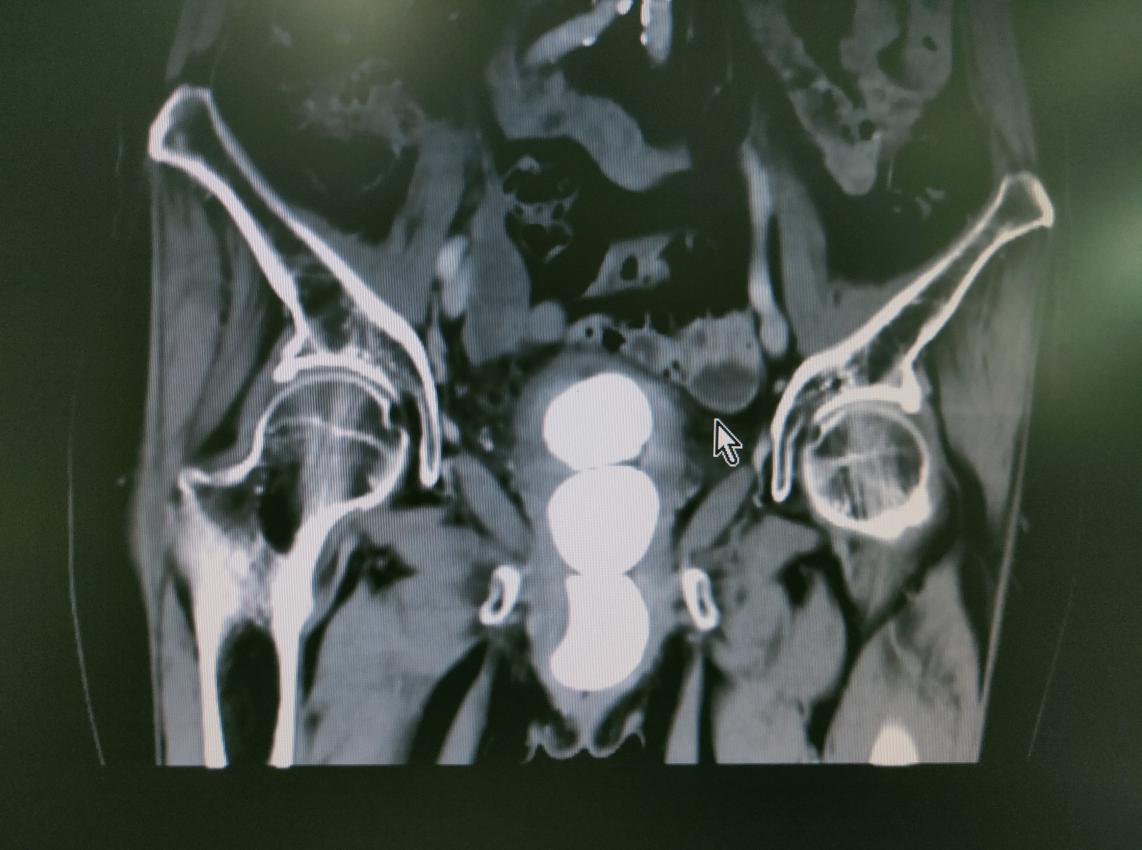

年近7旬的李奶奶一年前因脑出血导致半身瘫痪,且长期卧床并伴有排尿困难,CT检查发现膀胱中有三颗鹌鹑蛋大小的“舍利子”,俗称结石,而且结石周围有许多血块。

片中清晰可见的三颗“舍利子”(结石)

李奶奶一家慕名来到了附属医院泌尿外科寻求帮助,经检查发现,患者体内三颗结石平均大小4×4cm,手术指征非常明确,但患者基础病多,脑梗病史,身体状态较差,这极大的增加了手术的风险性,在泌尿外科主任蒋雷鸣的指导下,李勇平副主任医师、李均铭医师为其实施了“全麻下经尿道膀胱结石钬激光碎石术+膀胱血块清除术”。四十分钟后,手术结束,过程非常顺利。

三颗鹌鹑蛋大小结石